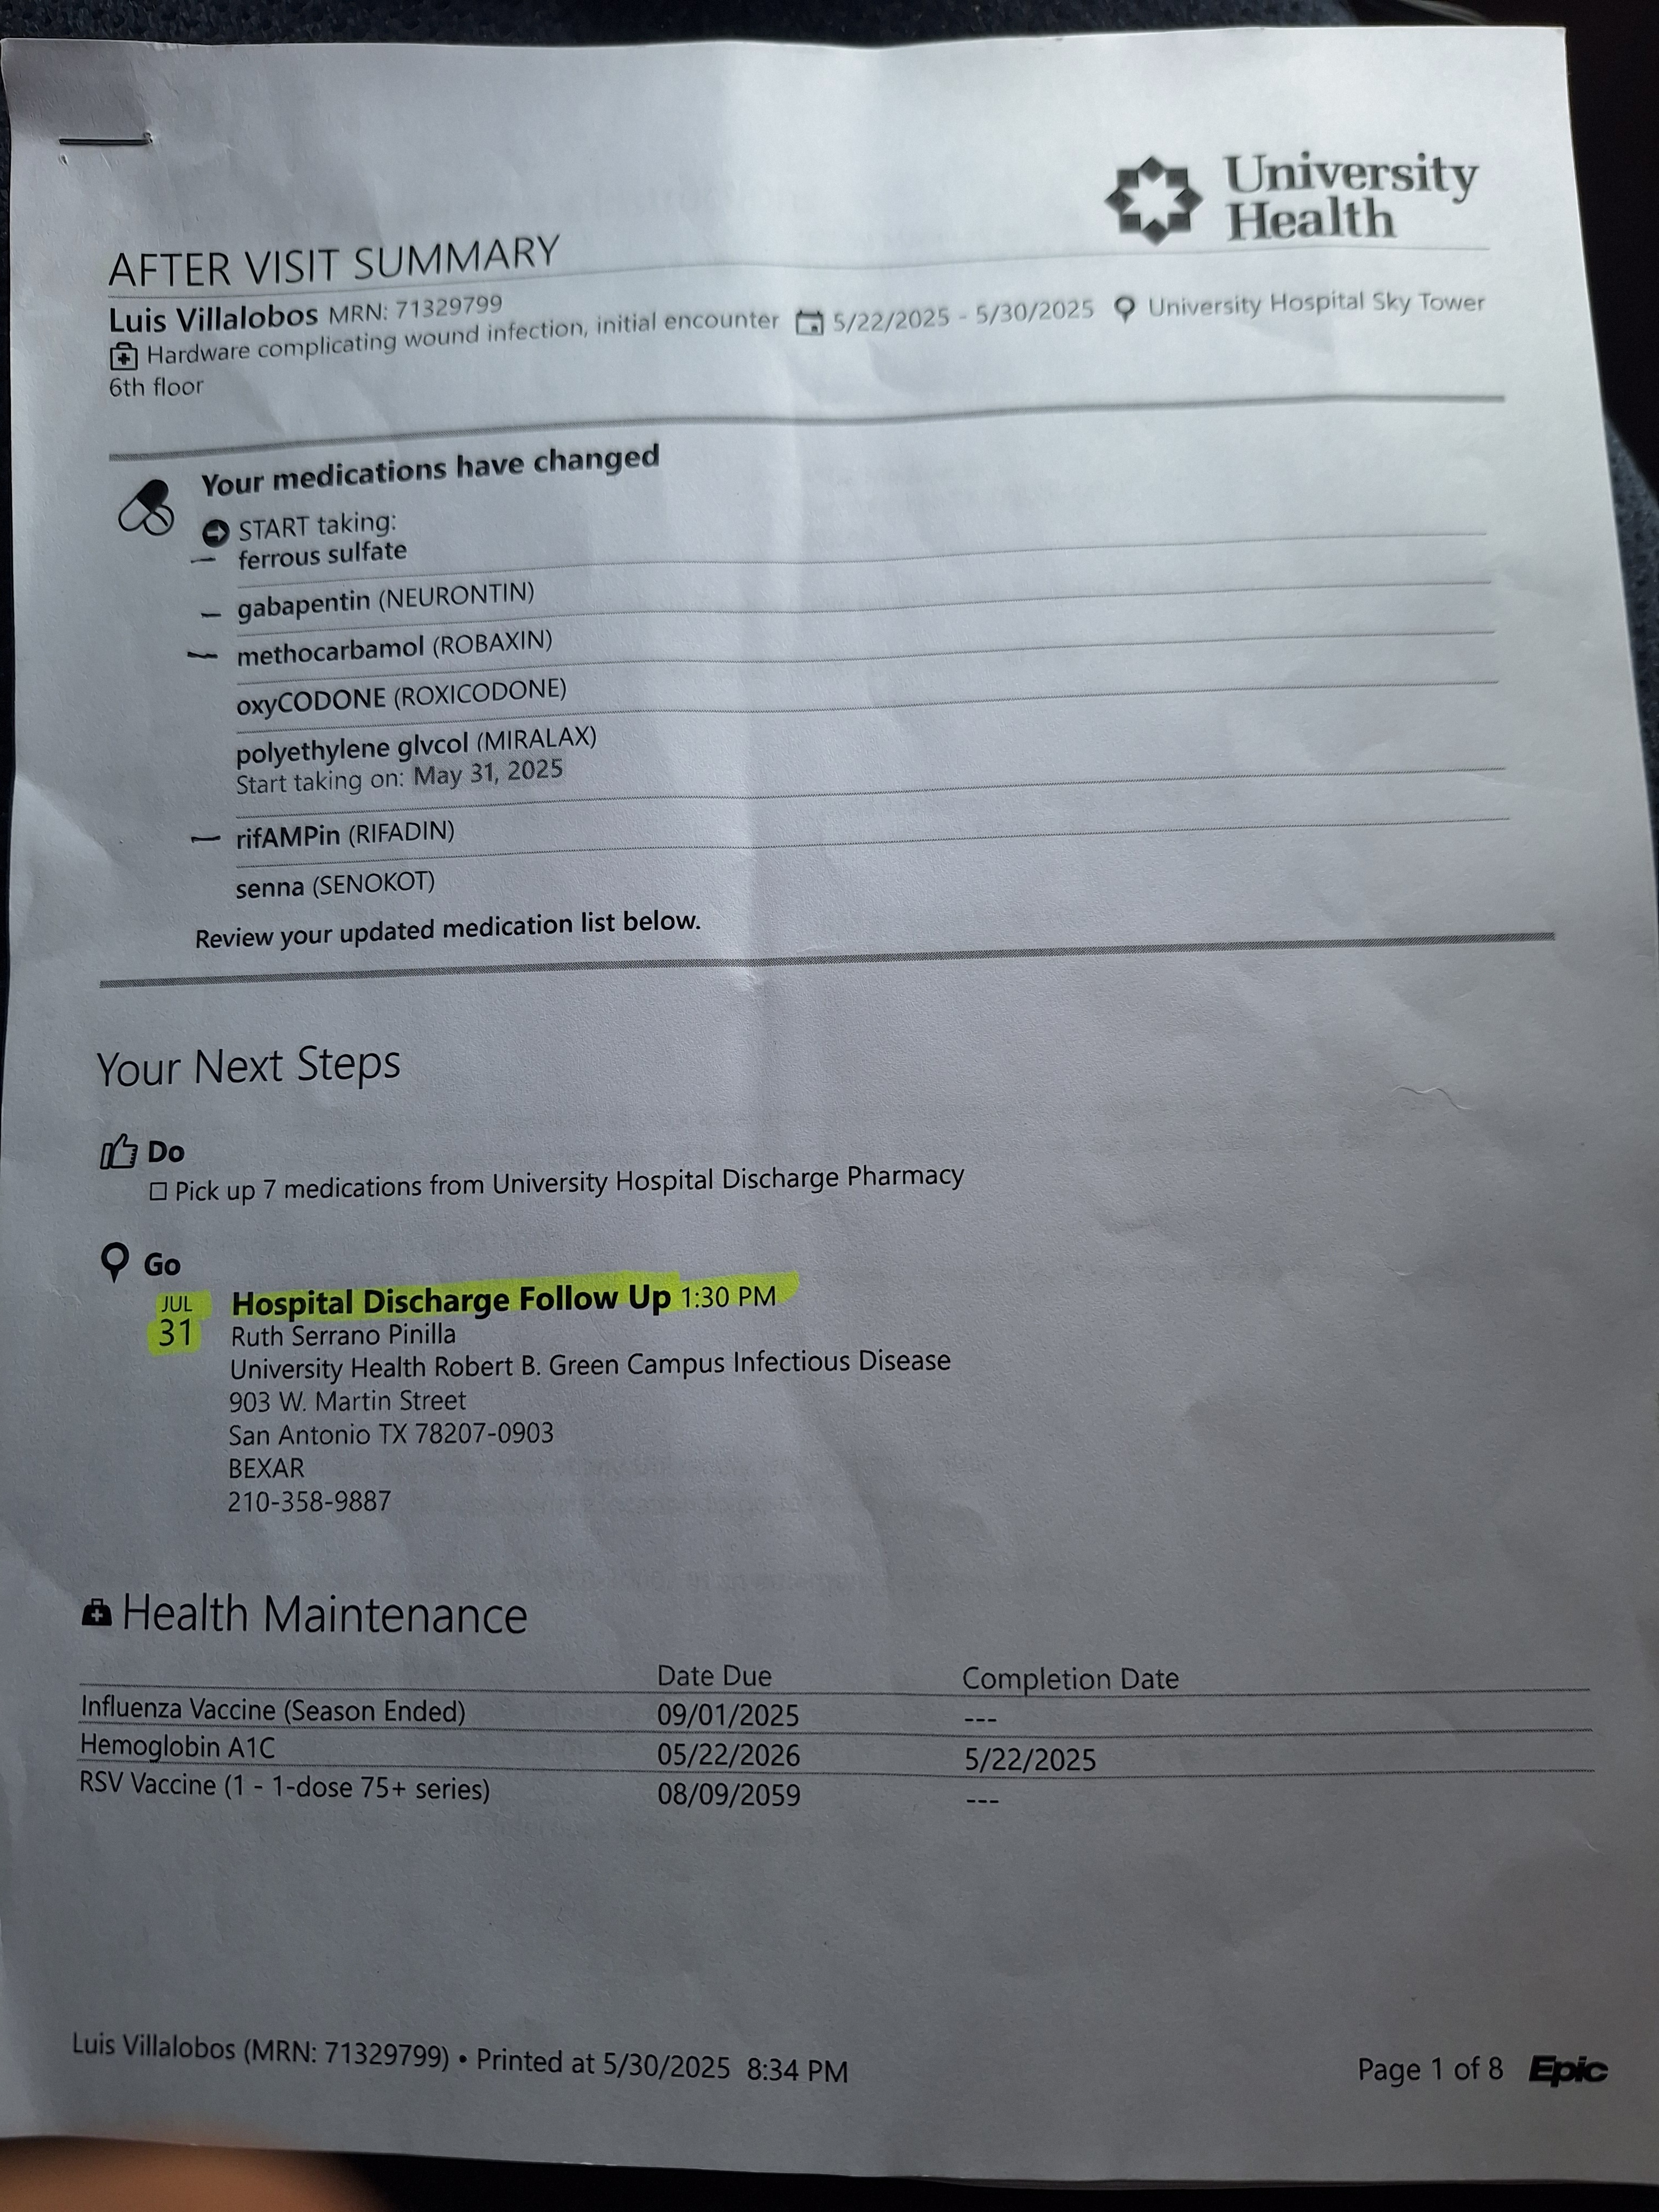

To help you understand the extent of my medical journey, I've included a picture of my discharge paperwork, which reflects the severity and ongoing nature of my condition.

Para ayudarles a comprender la magnitud de mi viaje médico, he incluido una foto de mi informe de alta hospitalaria, que refleja la gravedad y la naturaleza continua de mi condición.